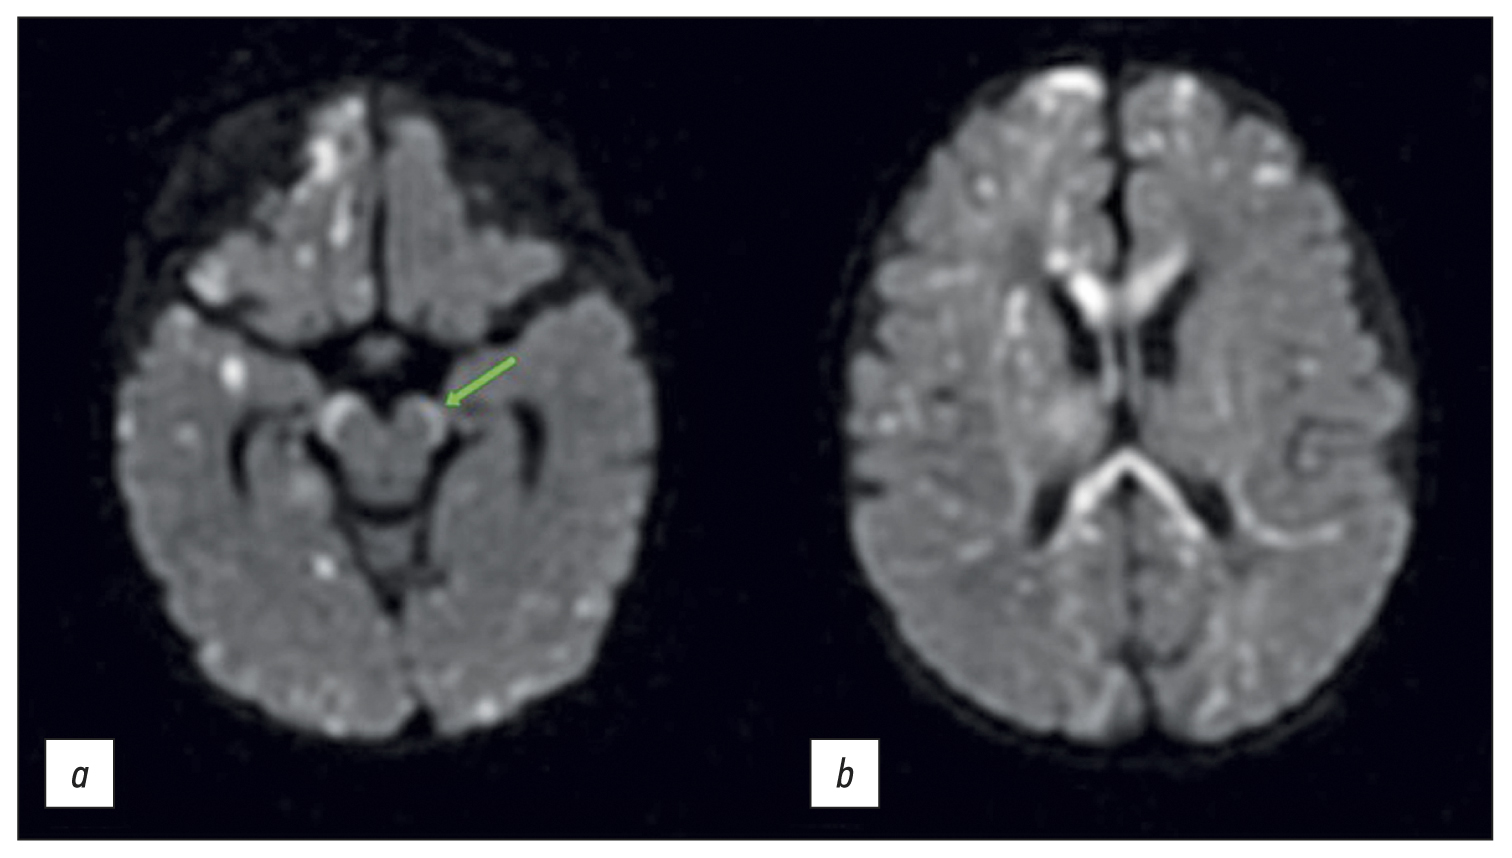

Multiple small (min. 2 mm) restricted diffusion lesions were found in the deep white matter, in and under the cortex, in the corpus callosum, posterior limb of the internal capsule, cerebral peduncles, along the corticospinal tract, and other tracts (Figure 2). Changes in the spinal pathways can be interpreted as either direct injury from incontinentia pigmenti or an early indicator of Wallerian degeneration (pre-Wallerian condition). The latter is characterized by spinal tract injury caused by neuron death and the degradation of the myelin sheath [14]. Small patches of restricted diffusion were regarded as tissue necrosis (infarctions).

Fig. 2. Diffuse-weighted brain images in the axial plane: (a) the arrow shows the hyperintense signal from the spinal tracts in the brain peduncles and (b) multiple lesions and involvement of the corpus callosum.